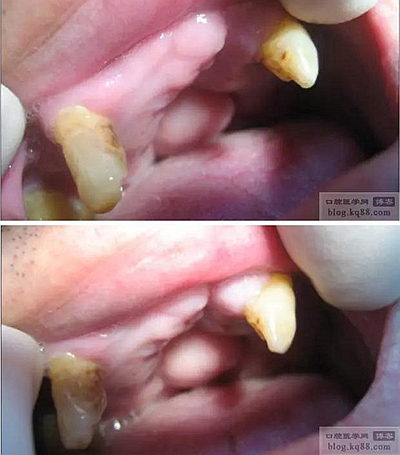

患者:某男,40歲,先天唇腭裂,年幼時(shí)做唇腭裂修補(bǔ)術(shù),來診時(shí)上下牙有不良修復(fù)體,上頜僅余有左上3、右上3、6三顆牙,且均有牙根外露。經(jīng)熟人介紹來診。

患者來診時(shí)照片和口內(nèi)照片,可以看到修補(bǔ)腭裂后硬腭在中央部位形成的軟組織包塊,周圍留有縫隙與鼻道相通。

左上3、右上3RCT后截冠,備樁洞,拆除下頜不良修復(fù)體。